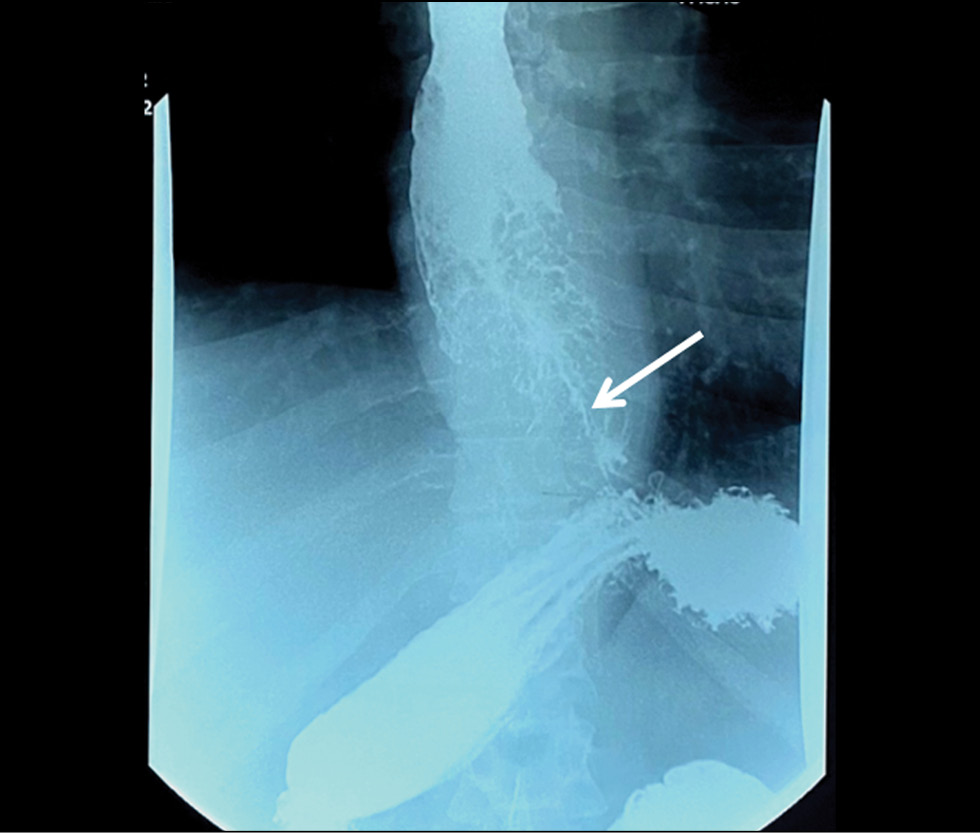

Barium-contrast upper gastrointestinal X-ray findings were suggestive of an extended mass lesion in the middle and lower thirds of the esophagus with luminal stenosis (Fig. 1).

Fig. 1. X-ray of the esophagus. Circular narrowing of the esophagus, a thin channel for the entry of barium suspension (indicated by an arrow).